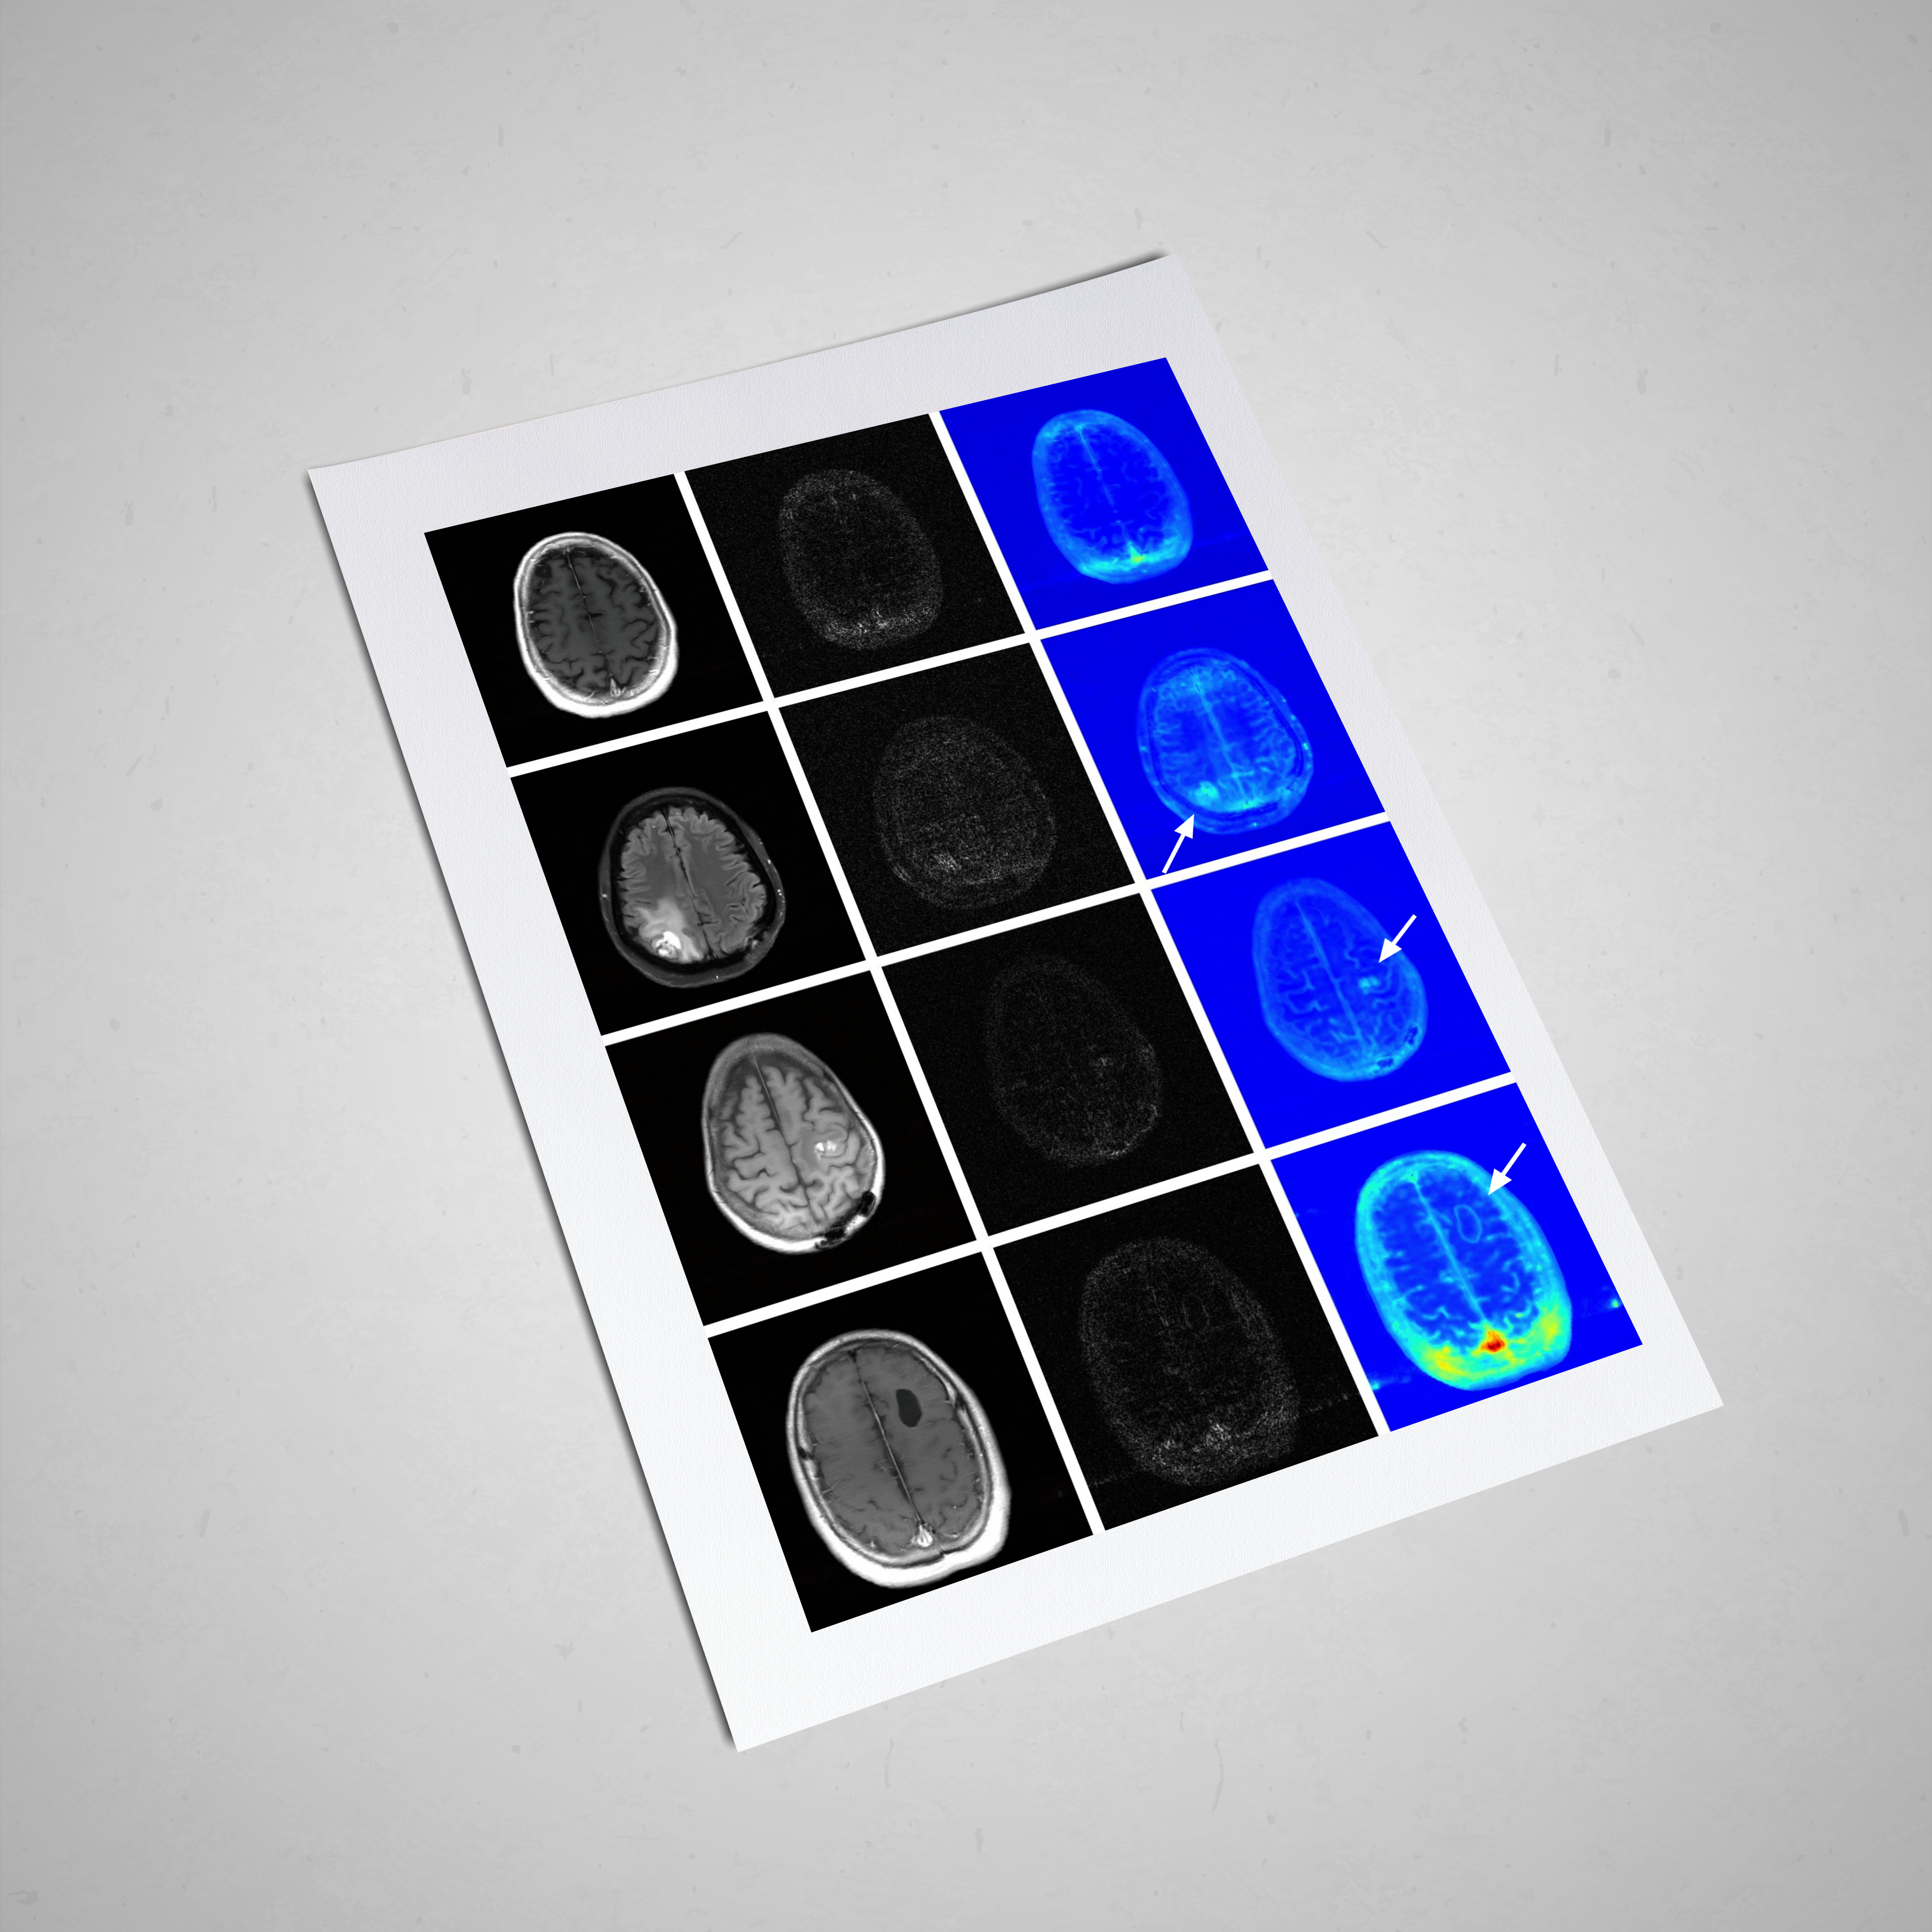

Supervised Learning-based EPT

Global Maxwell Tomography

Physics Informed EPT

Physics Informed Learning-based EPT